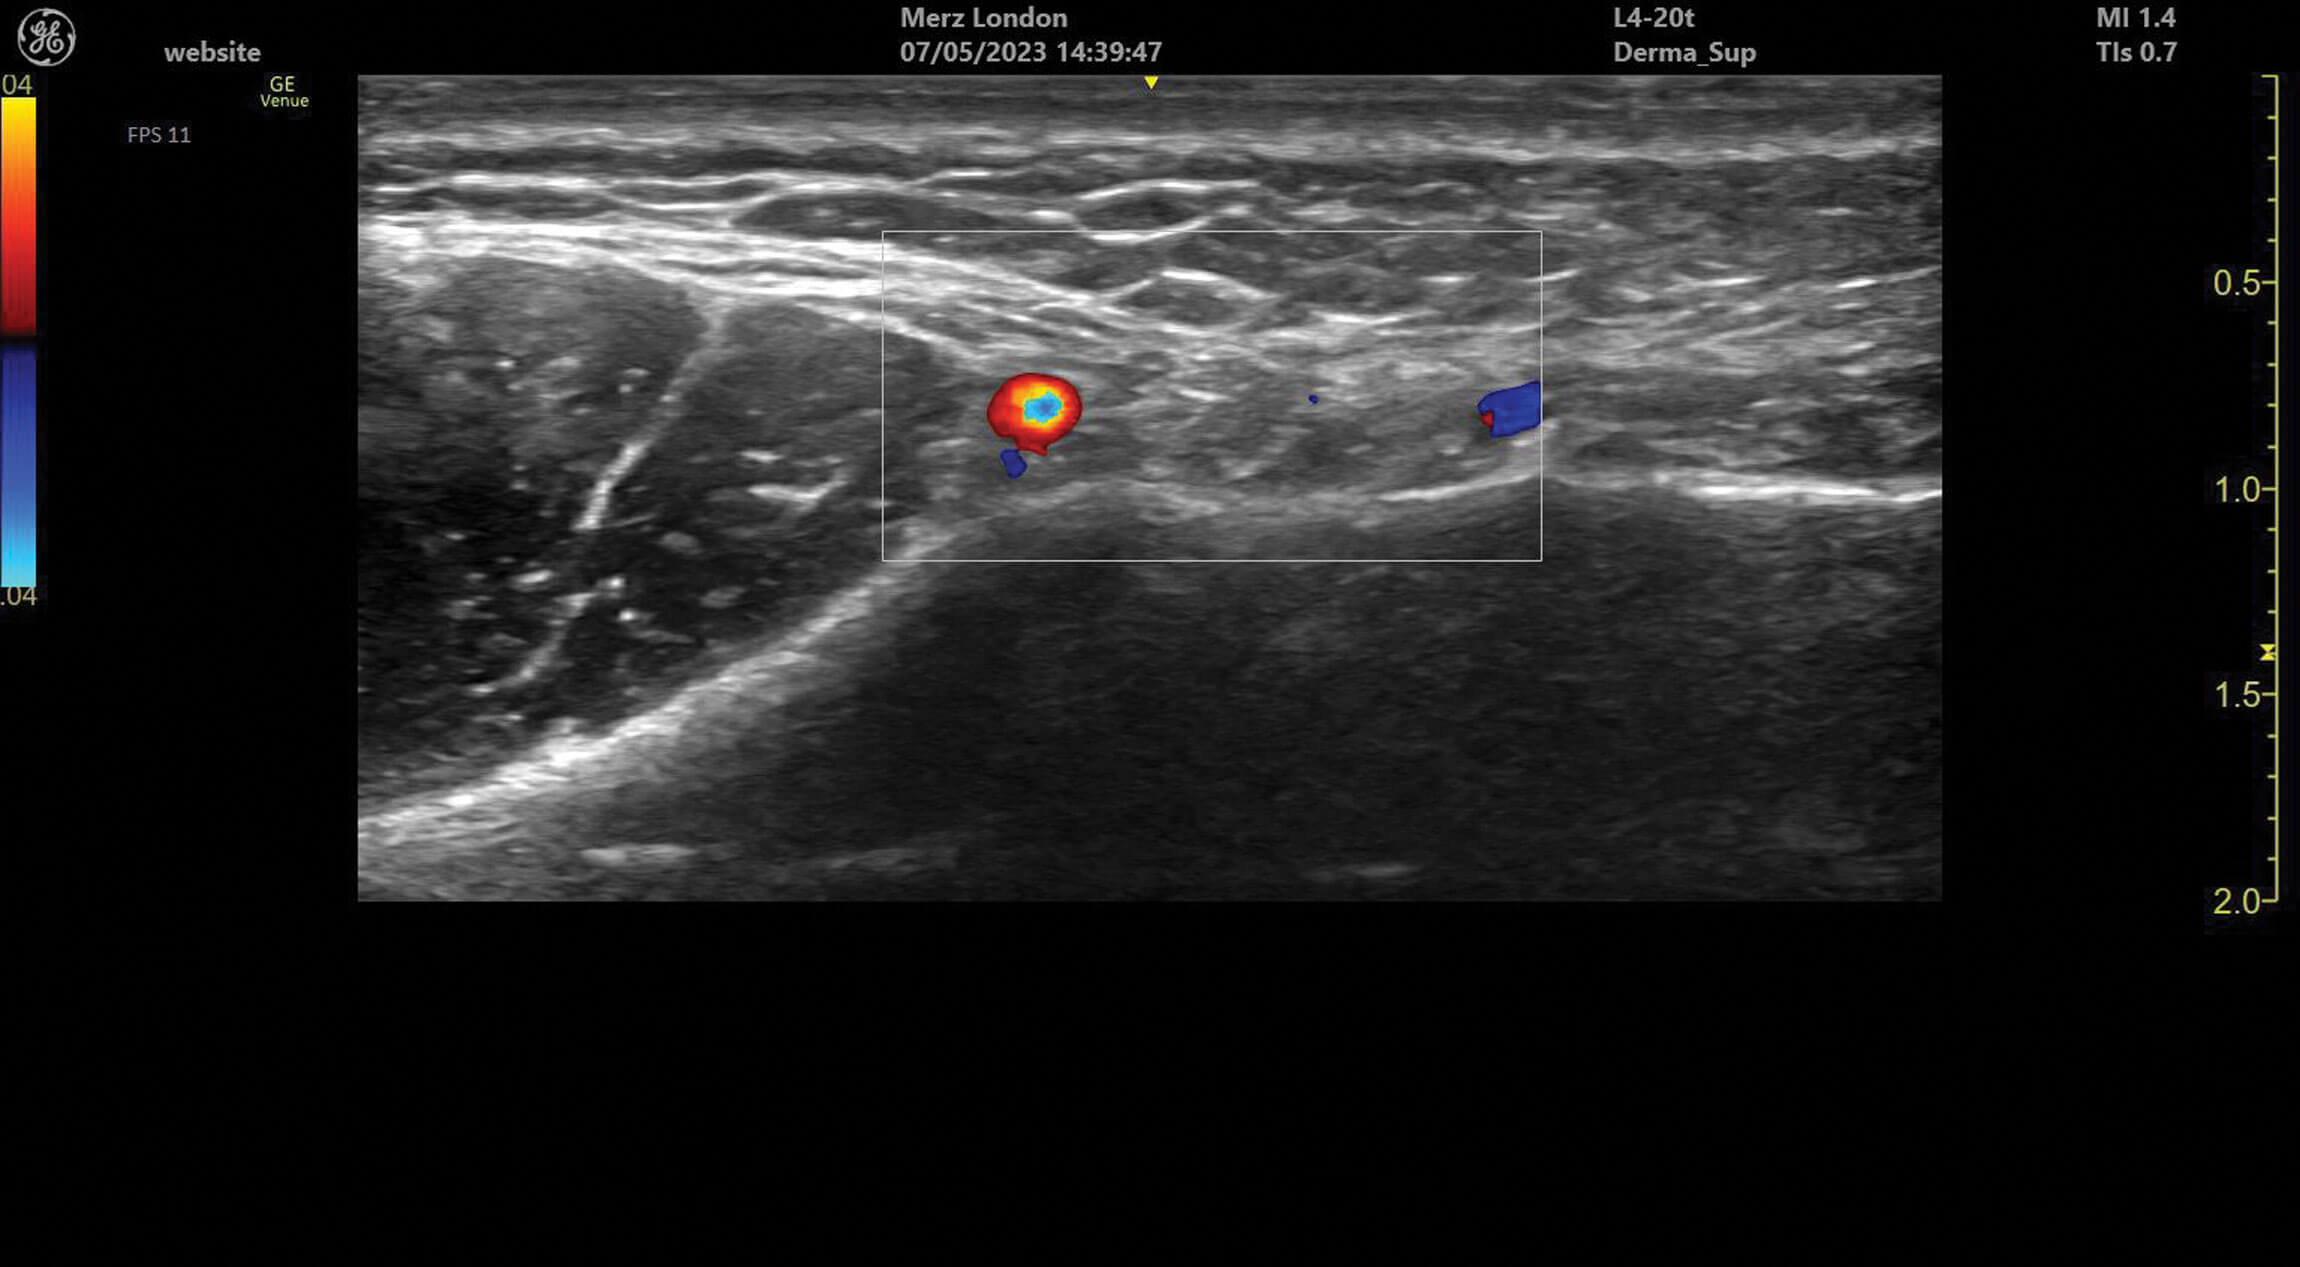

Figure 1: The facial vein and facial artery identified medial to the masseter in the facial plane of the lower face.

Ultrasound doppler can be used to assess blood vessel flow prior to treatments but can also help identify abnormalities in blood supply after filler treatment. Vessels can be identified and tracked in the tissue allowing for the observation of any anatomical variation. Blood vessels always appear as anechoic structures on ultrasound but, when using a colour doppler, flow can be detected either towards (red) or away (blue) from the ultrasound probe [1].